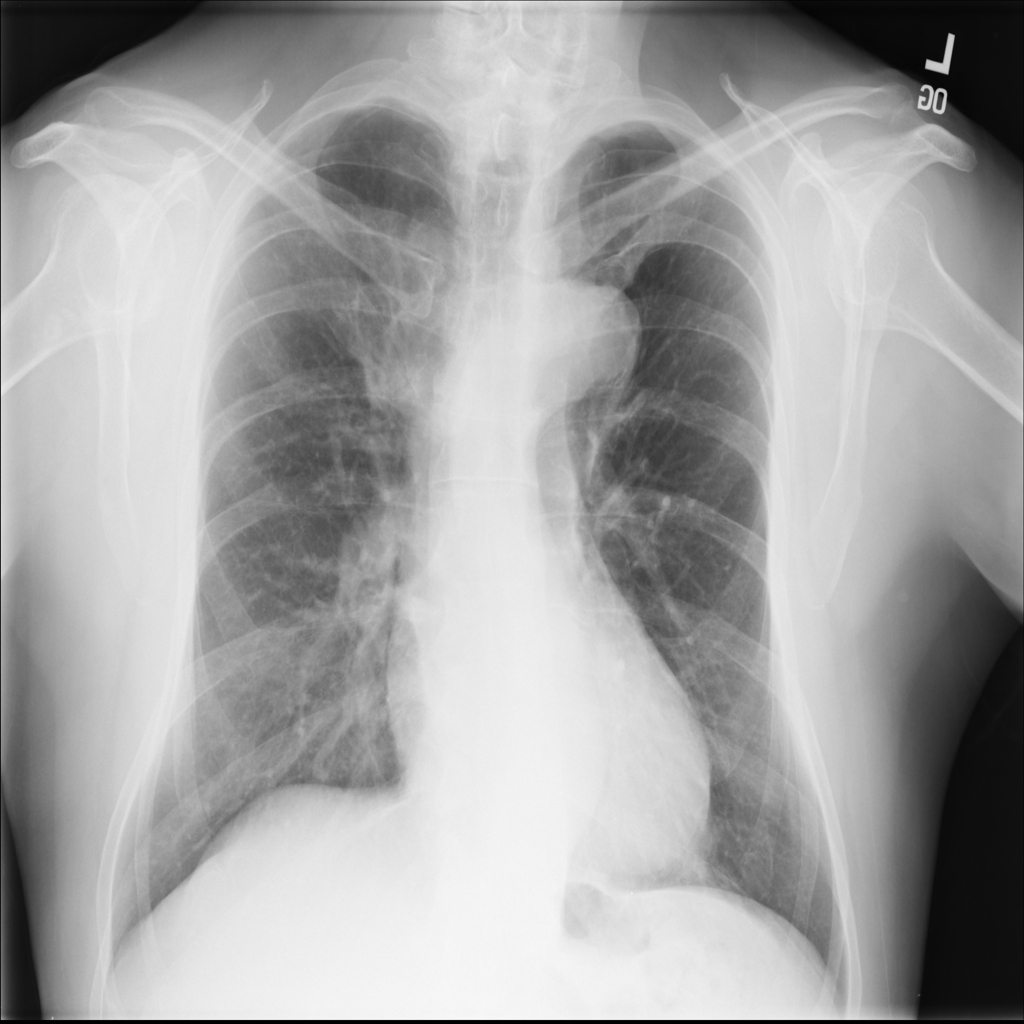

PAT-C048 · IMG-000Hernia

PAT-C048 · IMG-000

PA